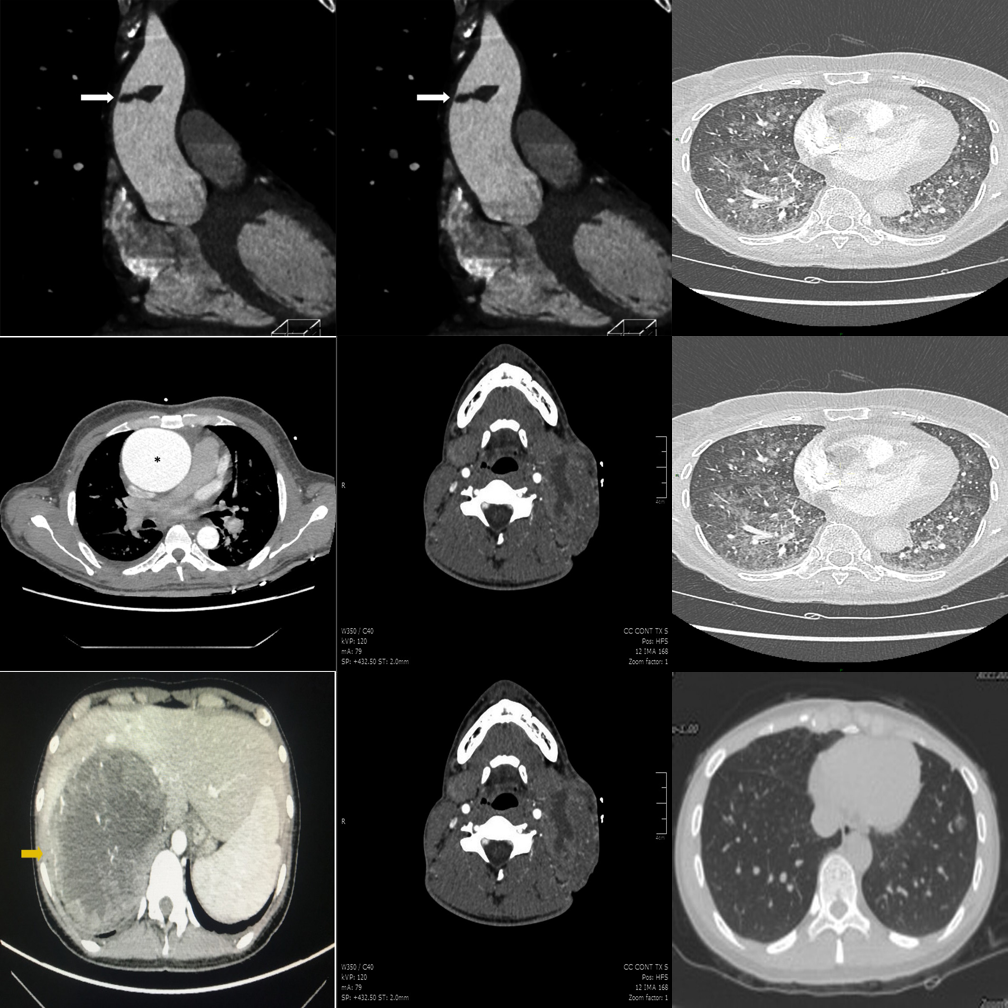

High-saliency clinical failures: surgical hardware, fractures, gross pathology.

Even the best model (MedGemma: 53.5%) fails nearly half the time on clinical hardware detection.

Open-ended generation reveals weaker grounding than constrained MCQ options.

Medical fine-tuning does not help — position bias dominates in open format.

Smallest proprietary model struggles with open-ended clinical reasoning.

When pointed directly at the outlier, the model can confirm differing modality.

Fails to recognize the modality difference even when the outlier is highlighted.

Medical VLM incorrectly denies an obvious modality mismatch.

Hallucinates an anomaly in the highlighted panel despite it being consistent.

"Always-find-something" bias is triggered by the red box visual cue.

Best negative control accuracy among medical VLMs — capable of restraint.